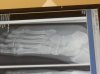

Can anyone please tell me if this is a jones fracture. My first doctor told me it was a jones. Then asked to see a different doctor as wanted to request surgery and then this one told me it was not a jones. I have now had this 17 weeks, walking with pain. This xray was taken at 6 weeks (I know its not the best image). Can anyone please confirm whether this is a jones.

It does look like the xray I had taken for my Jones fracture. The only diff between your xray and mine is that it looks like your fracture goes part way across the bone and mine looked like it went all the way across. Yours also seems to have a small gap where the break is and mine didn't have that. Mine just looked like a small line straight across the bone. I am sure this doesn't help you much but I know how frustrating on this site it is to not get anyone to answer.